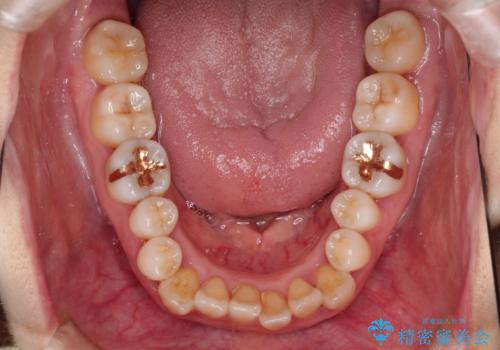

インビザラインによる矯正治療(非抜歯) 上下前歯の開き(開咬)と上下のガタつき(叢生)の改善

- 上下の前歯の開き(開咬)と上下前歯にガタつき(叢生)が見られます。

マウスピース矯正ではメカニクス的に開咬へのアプローチが容易です。

インビザラインの特色を生かした歯牙移動計画を作成し、非抜歯にて治療を行いました。

マウスピース枚数 初回36枚 + 追加26枚

概ね1年4ヶ月で治療完了しました。

マウスピース矯正は開咬(オープンバイト)に対して有利な治療メカニクスを持ちます。

当院独自の工夫を随所に盛り込み、狙い通りの治療結果が得られました。